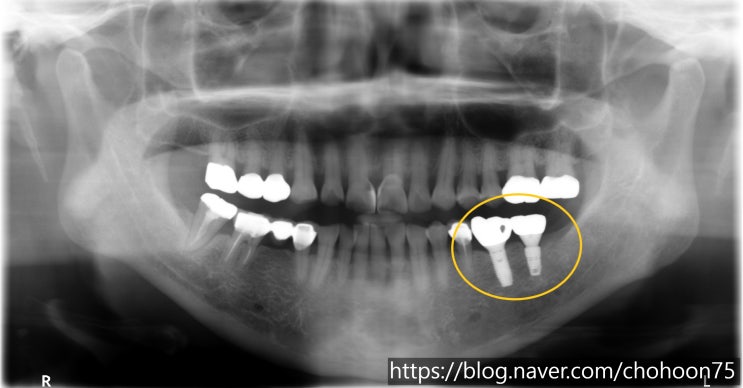

[조훈치과] 공간 확보를 위한 치아 교정 후 임플란트 식립 치료 증례

안녕하세요. 조훈 치과입니다. 치아 상실 후 적절한 치료가 이루어지지 않은 채 오랜 기간 방치를 하게 되...

[조훈치과] 뼈이식을 동반한 어금니 임플란트 치료 증례

안녕하세요. 조훈 치과입니다. 임플란트 뼈이식 꼭 필요한가요? 임플란트는 잇몸뼈에 인공 치근을 식립하고...

[조훈치과] 심한 치조골 파괴- 뼈이식이 선행된 임플란트 식립 치료 증례

안녕하세요. 조훈 치과입니다. 임플란트 식립 시 잇몸뼈의 양이 충분하지 않다면 임플란트 수술이 어려울 ...

[조훈치과] 임플란트 치료를 통한 교합 관계 회복

안녕하세요. 조훈 치과입니다. 치아를 상실한 채 오랜 기간 방치를 하게 되면 치아 간의 높낮이의 변화가 ...

[조훈치과] 치아 상실 후 임플란트 식립 치료 증례

안녕하세요. 조훈 치과입니다. 치아 상실의 원인은 여러 가지가 있습니다. 충치 및 치주 질환이 악화된 경...